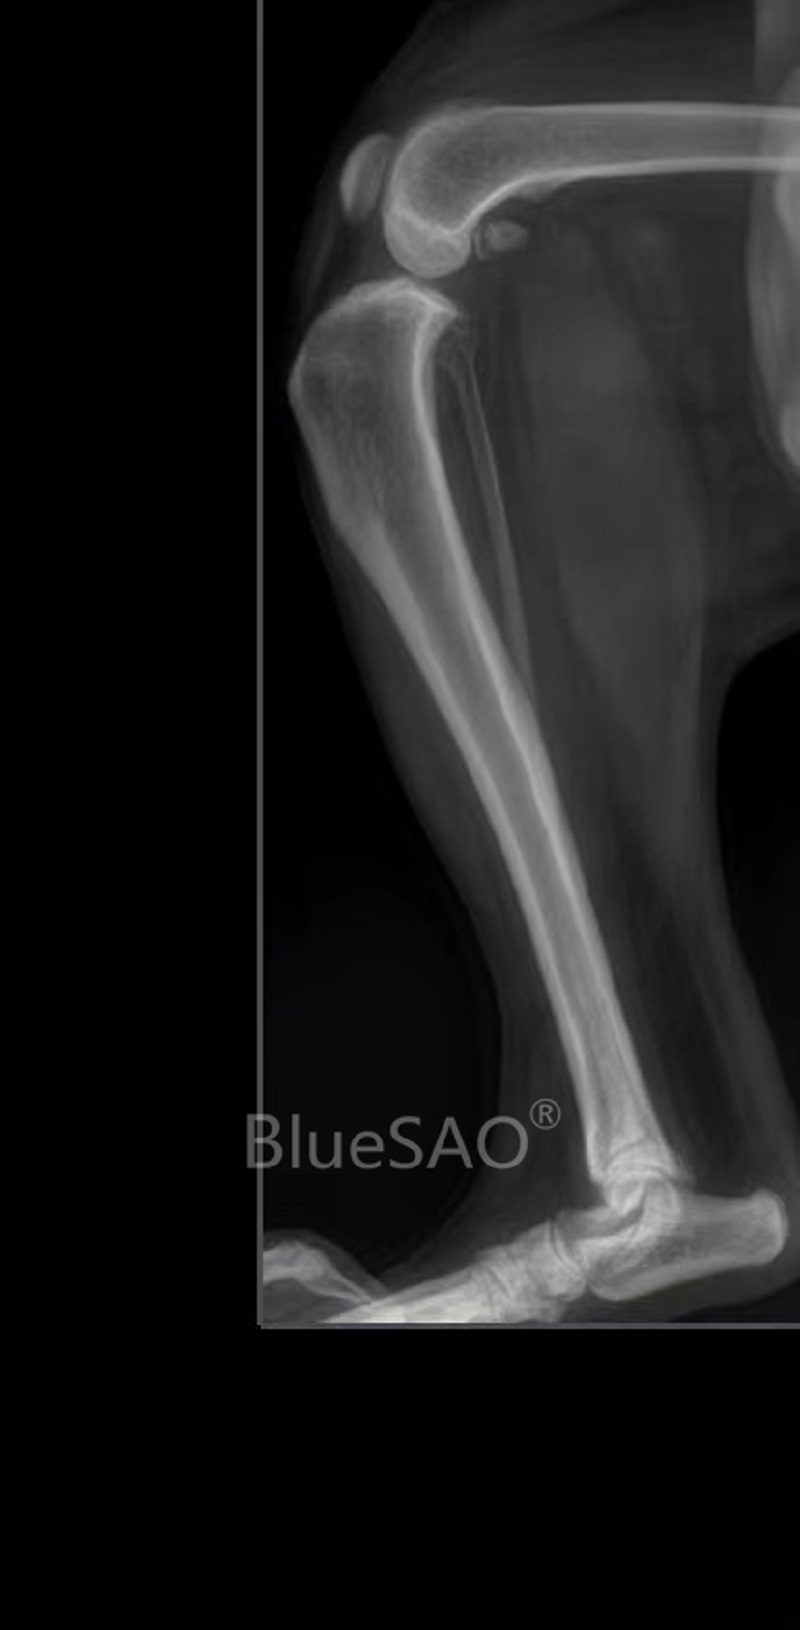

#Dog# #84Months# #18kg# #knee joint-other position-rupture of cranial cruciate ligament# #knee joint-other position-TPLO#

A dog, named Xiaohuang, 7 years old, male, 18kg. The pet owner took the dog to the doctor for persistent limping in the right hind limb. The right knee-joint was unstable. The drawer test was positive. Cranial cruciate ligament rupture was diagnosed combining Digital Radiography imaging. We did a TPLO surgery for him by using BlueSAO TPLO-8.5mm R pure titanium locking plate and a 18-gauge saw blade. The surgical effect was good and we look forward to a speedy recovery.